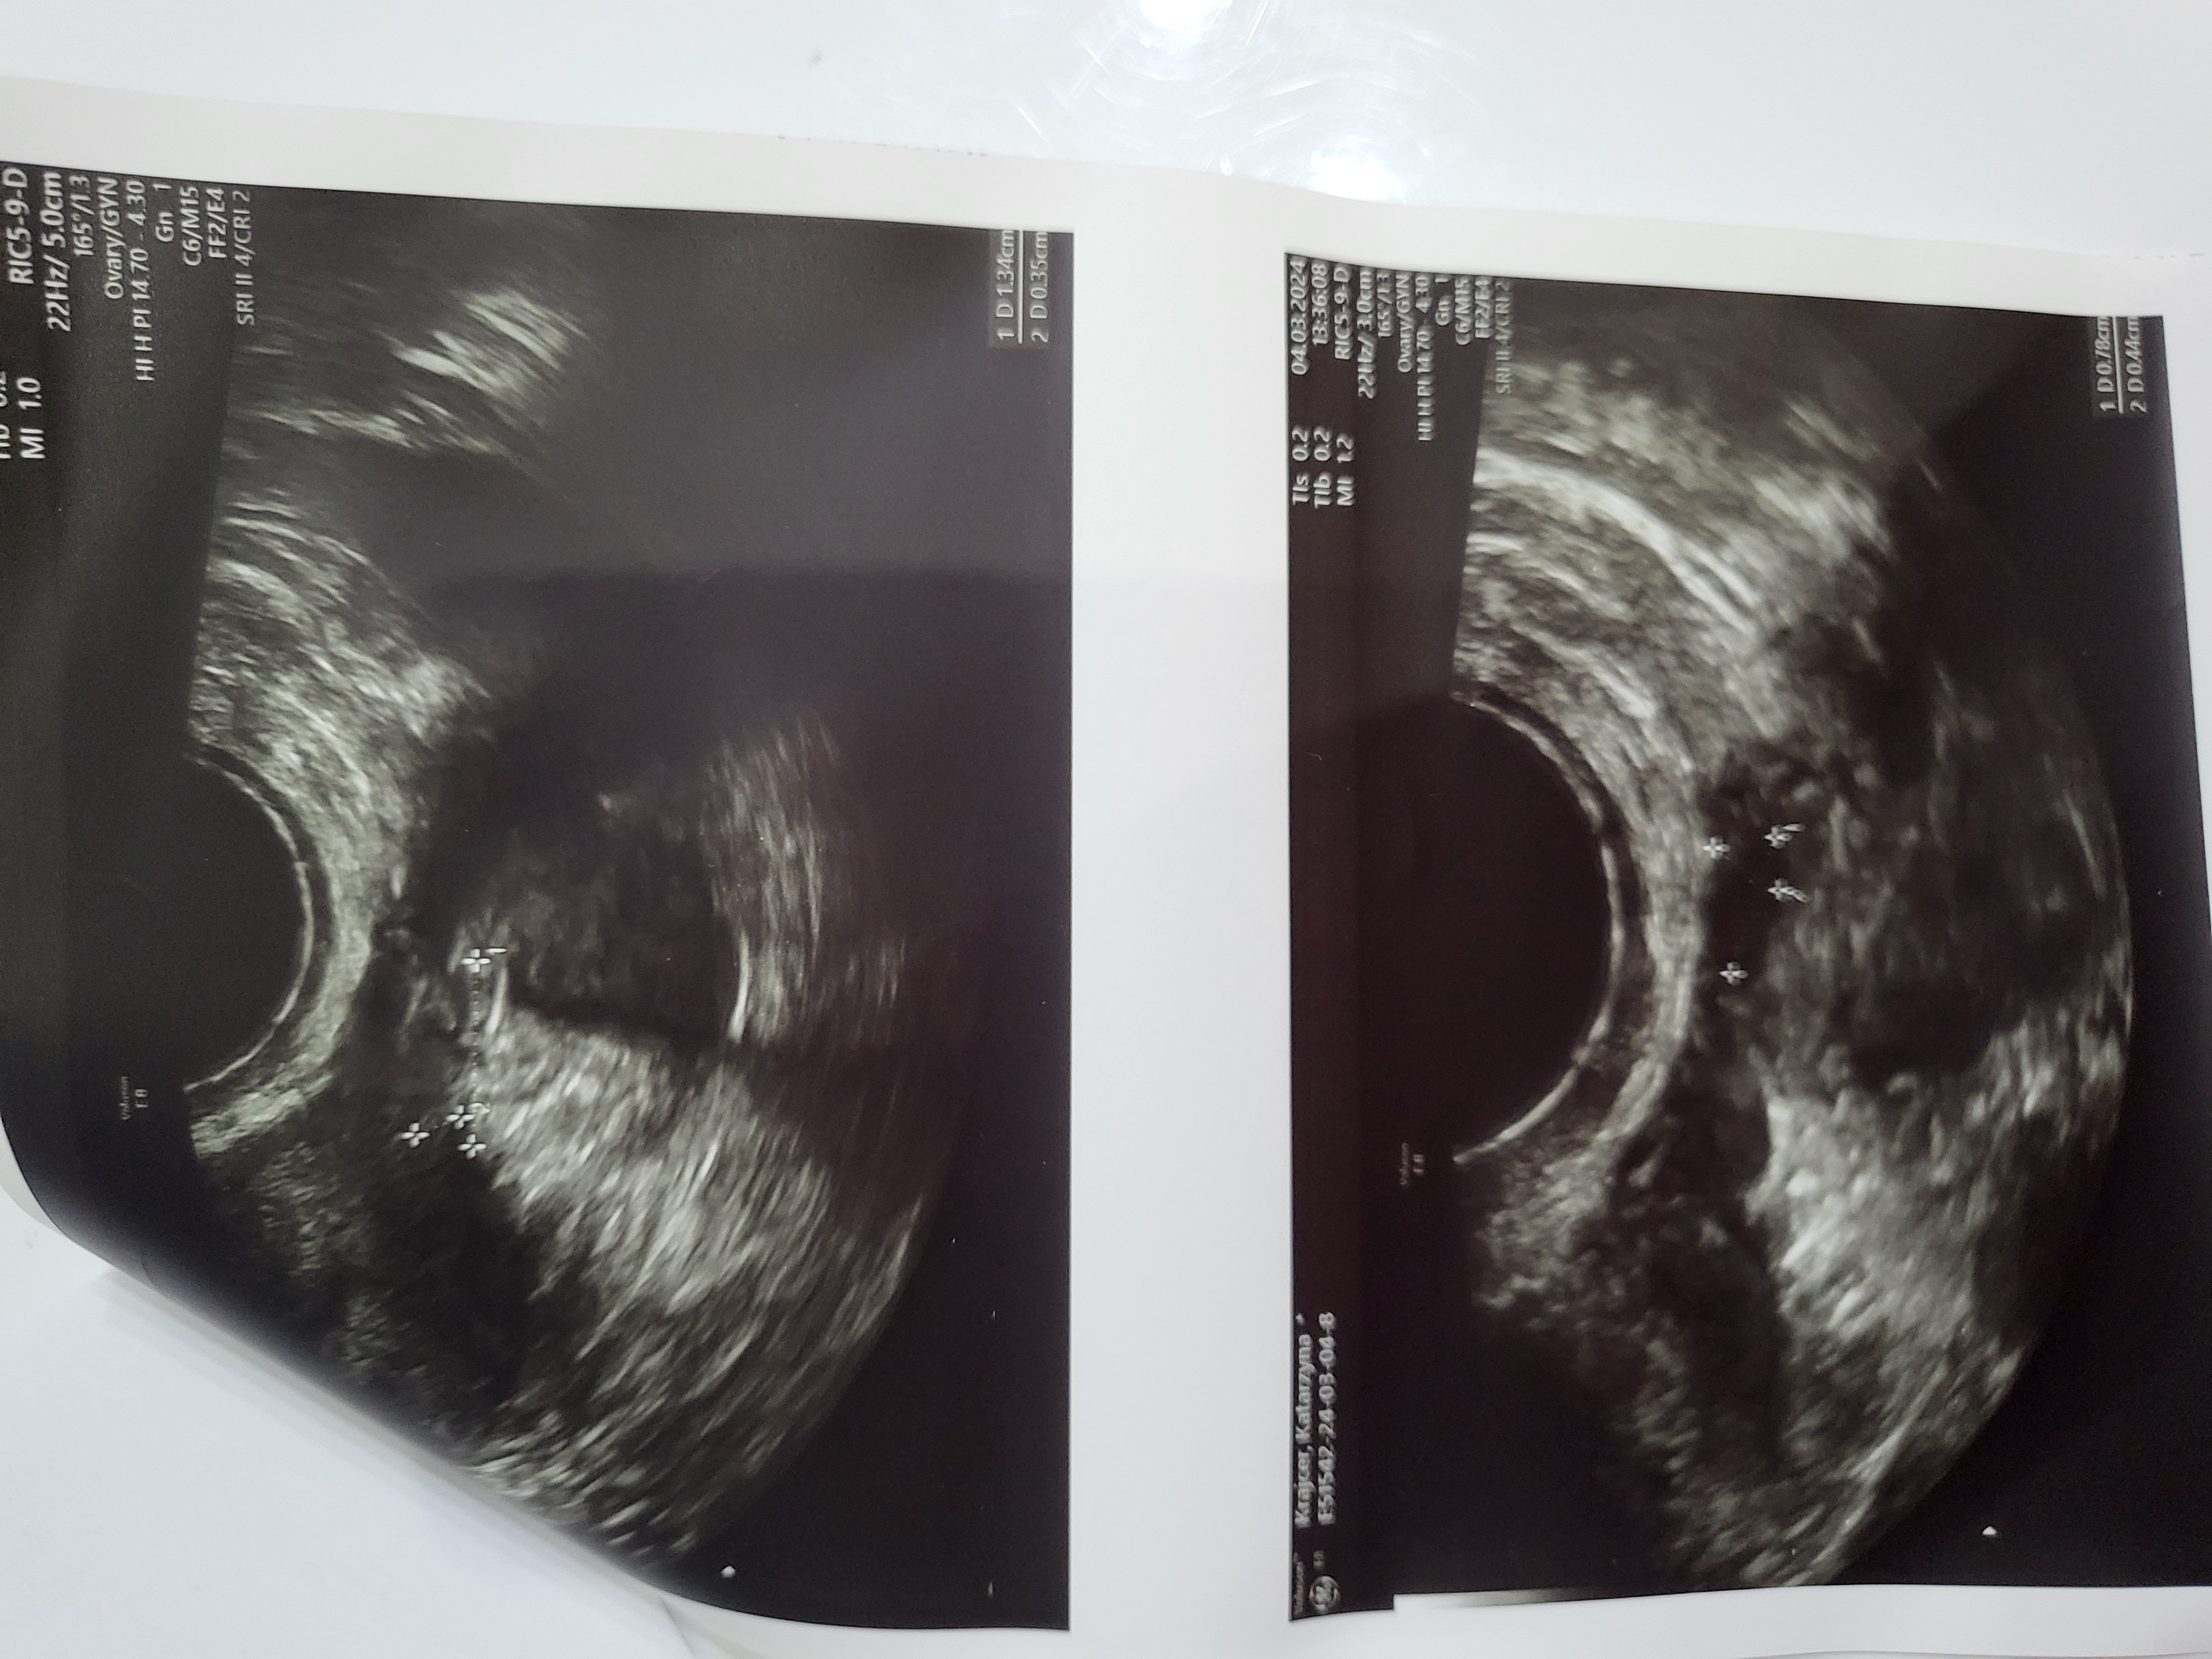

Pani doktor przy każdym USG transwaginalnym odnajdywała torbiele: mniejsze, większe, mnogie, dwukomorowe – lecz były ,, do obserwacji”. Pomimo przyjmowania tabletek hormonalnych one nadal się pojawiały. W celu diagnozy skierowano mnie na laparoskopię, która się nie odbyła ze względu na planowaną w niedługim czasie operację usunięcia dwóch przepuklin pachwinowych.

Moje wizyty u ginekologa odbywały się 1-2 razy w miesiącu, jednak cały czas słyszałam, że torbiele trzeba obserwować.

Natychmiast umówiłam się na wizytę, która potwierdziła obecność torbieli. Dostałam po raz kolejny nic nie wnoszącą radę ,, trzeba obserwować”.

Postanowiłam umówić się na wizytę, która miała miejsce 04.03.2024r.

Dr Karmowski prosił, abym usiadła na fotelu i po dokładnym przeprowadzeniu badania opowiedział o wszystkim co mi dolegało. W końcu na swojej drodze spotkałam lekarza, który chce i potrafi mi pomóc.